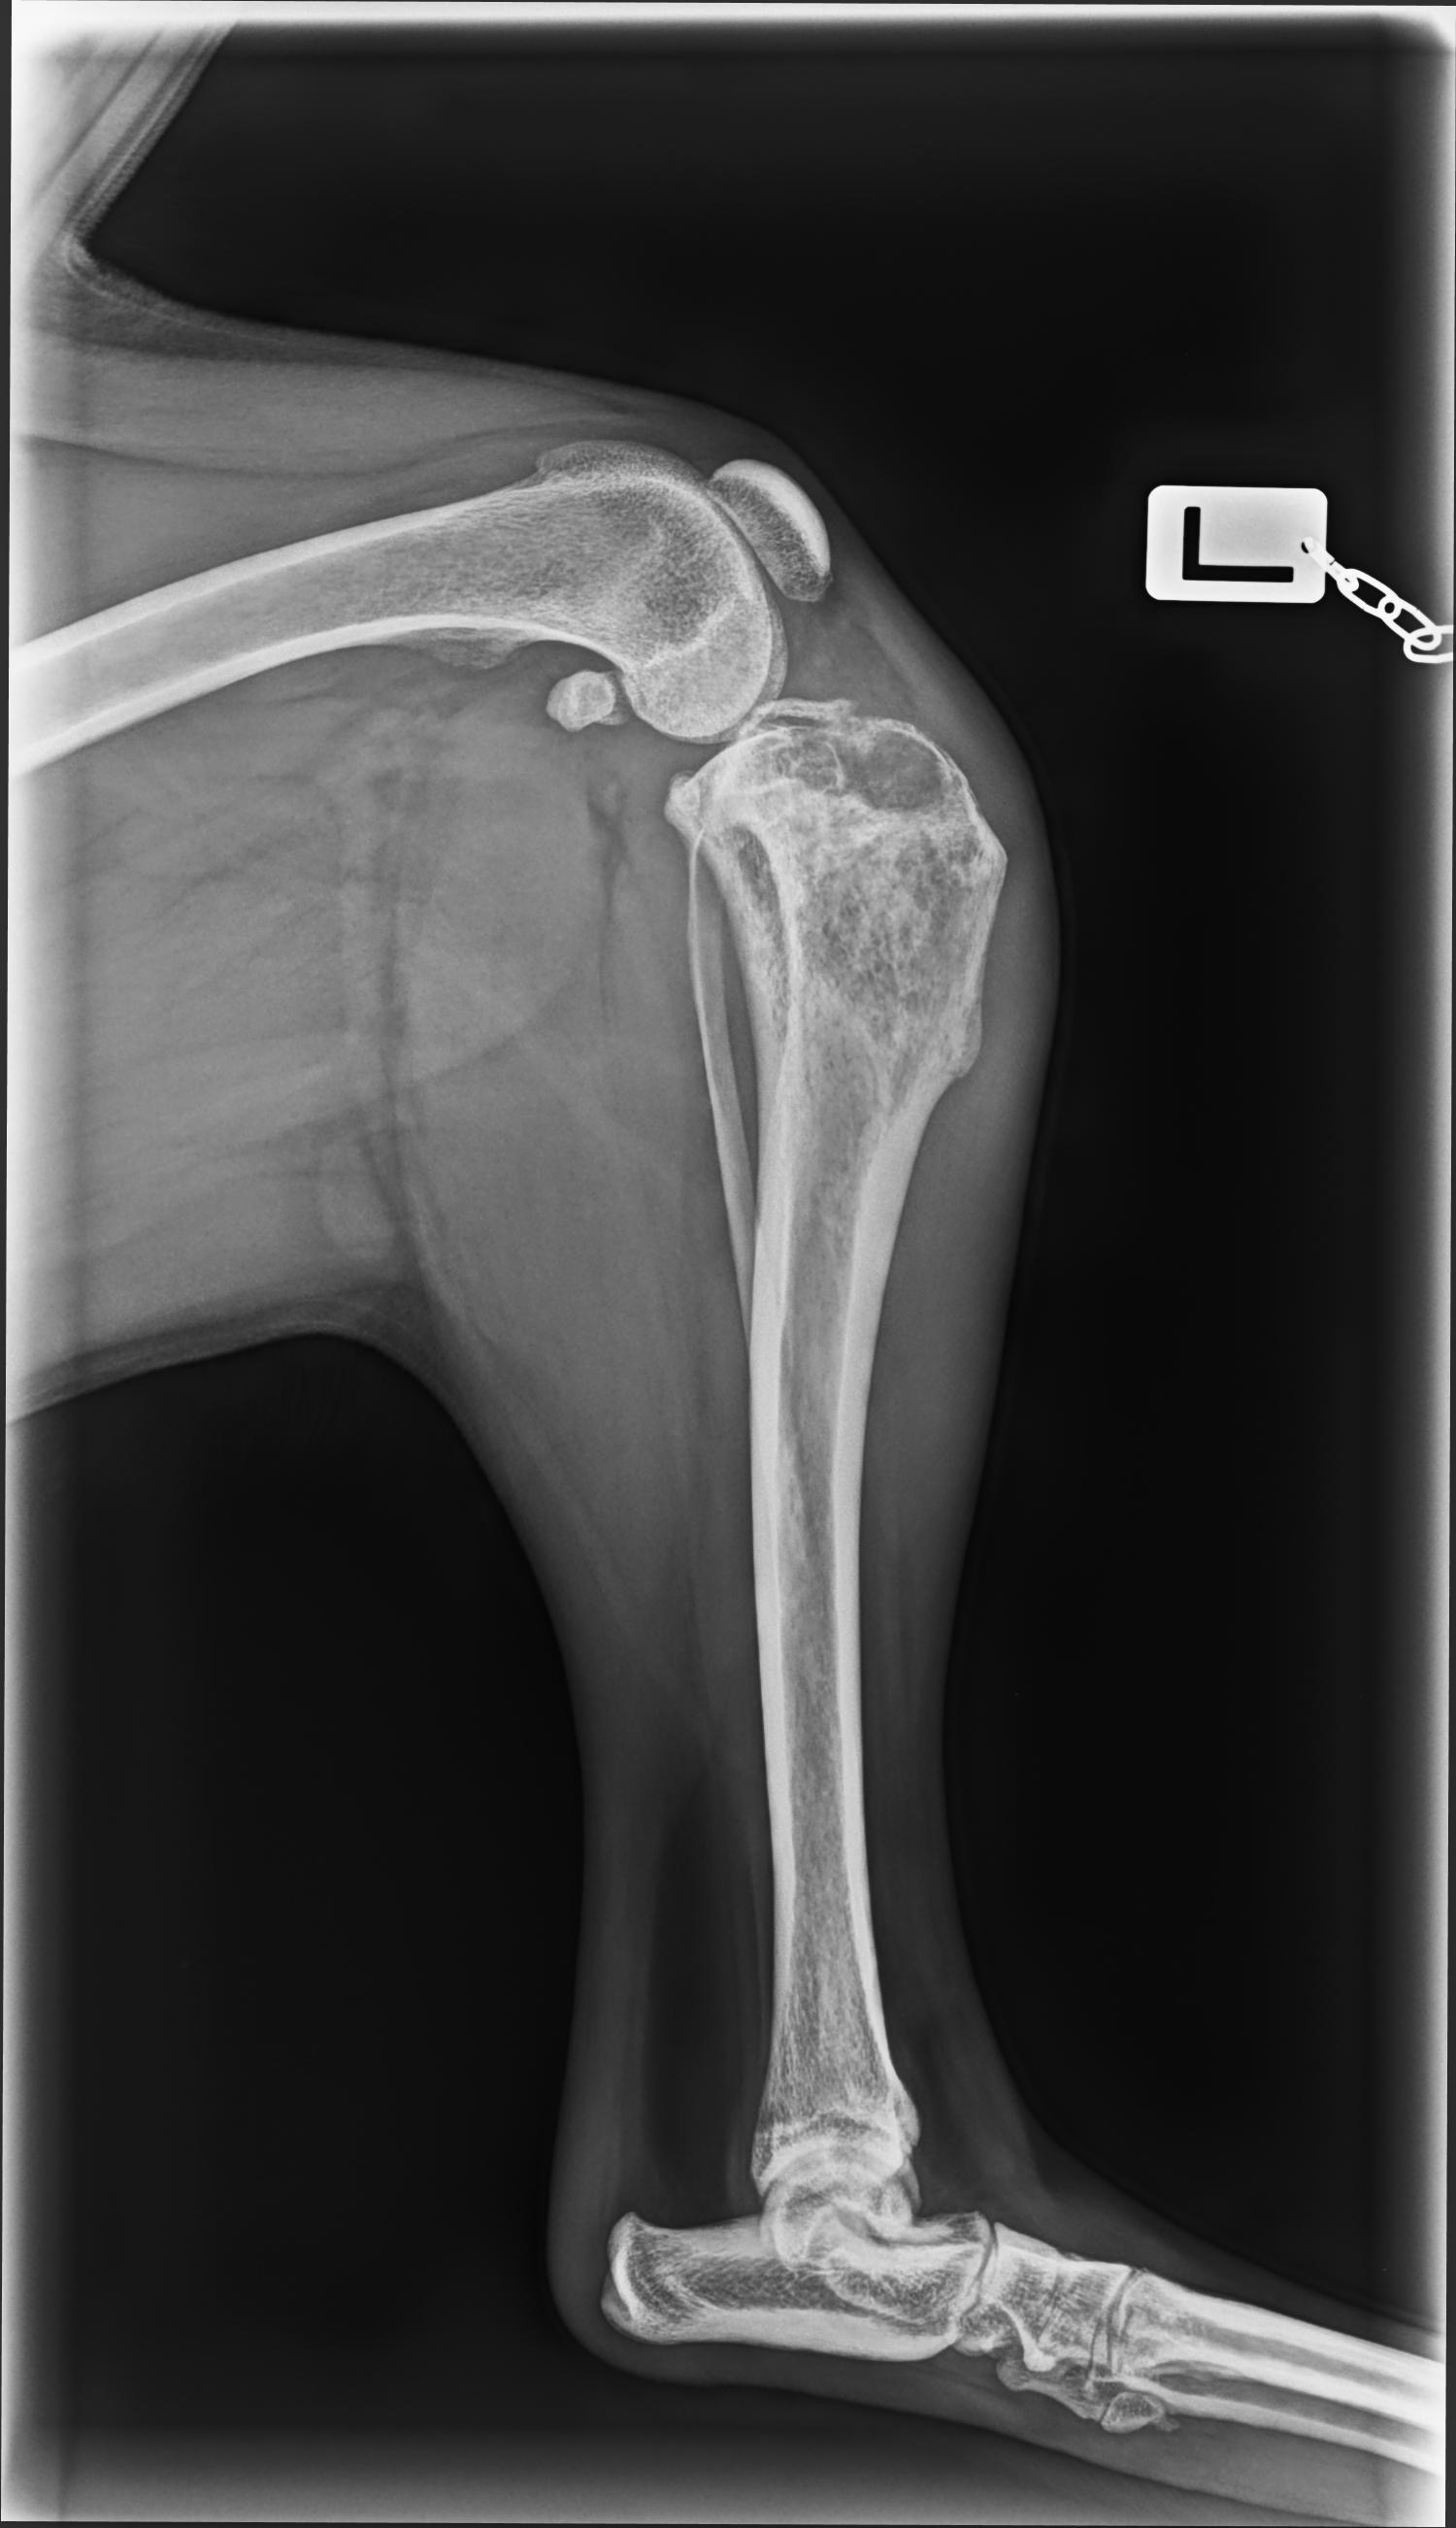

About two months ago, I started noticing something wasn’t right with his left leg. After vet visits and tests, I received the devastating news that Draco has cancer in his leg. Hearing that at such a young age has been heartbreaking.